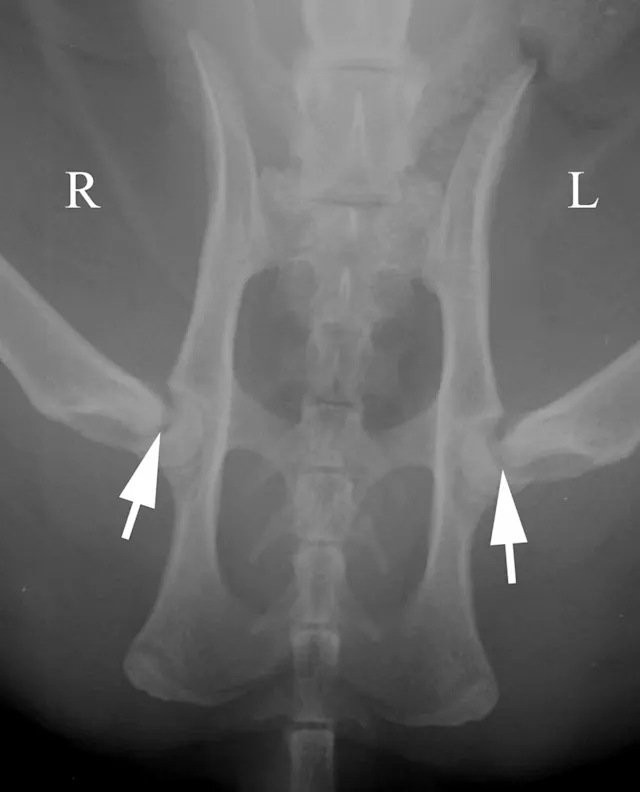

Oblique positioning will result in false assessment of dorsal acetabular rim coverage of the femoral head, as shown in Figure 2C. The dorsal acetabular rim (white arrows) appears to provide more coverage of the right femoral head and less coverage on the left side. When the patient is properly positioned, as in Figure 2D, it is evident that coverage of the dorsal acetabular rim (white arrows) is similar on both sides.